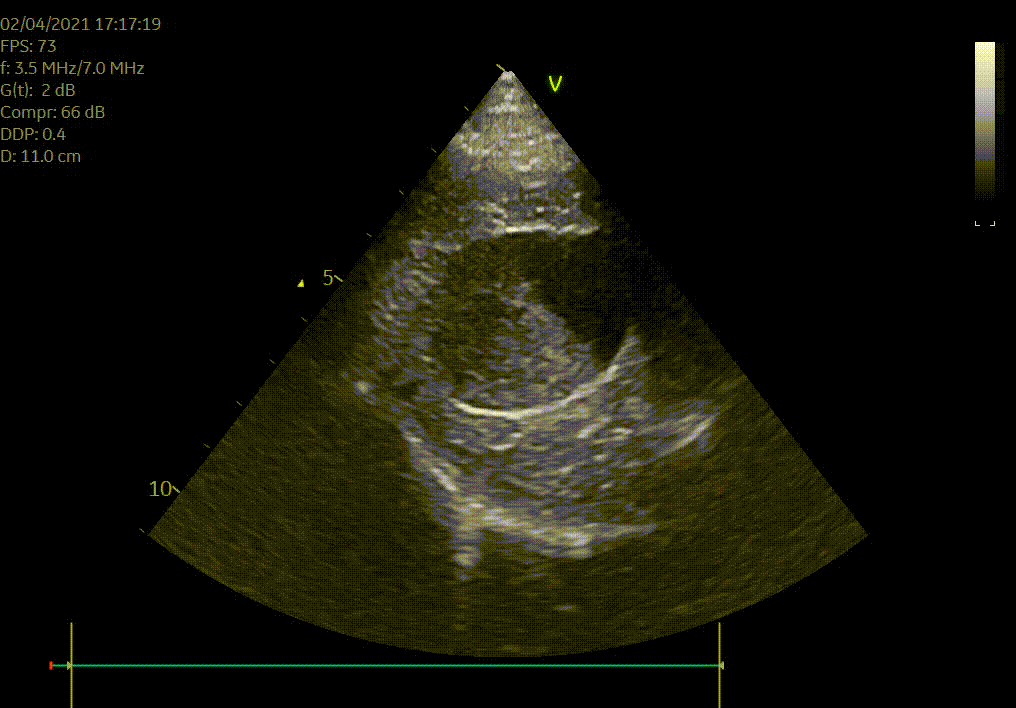

Heeft uw hond of kat een hartruis? Het is dan aangewezen om een echocardiografie (hartfilmpje) uit te laten voeren om na te gaan of er best ondersteunende hartmedicatie moet opgestart worden. Met een echocardiografie gaan we na of het hart normaal gevormd is, normaal werkt en beoordelen we de ergheidsgraad van eventuele kleplekken.

Hartonderzoek - Echocardiografie - Electrocardiografie (EKG) - Radiografie

Waarom een echografie laten uitvoeren? Echografie geeft een goed beeld van de inwendige organen zoals het hart, de longen, de maag en darmen, de milt, de lever, de galblaas, de nieren, de blaas, de baarmoeder...Met echografie is een drachtcontrole (zwangerschapscontrole) bij een kat vanaf 18-21 dagen en bij een hond vanaf 28 dagen mogelijk.

De kwaliteit van een echografie is afhankelijk van de lichaamsbouw en de mate dat je hond of kat meewerkt.